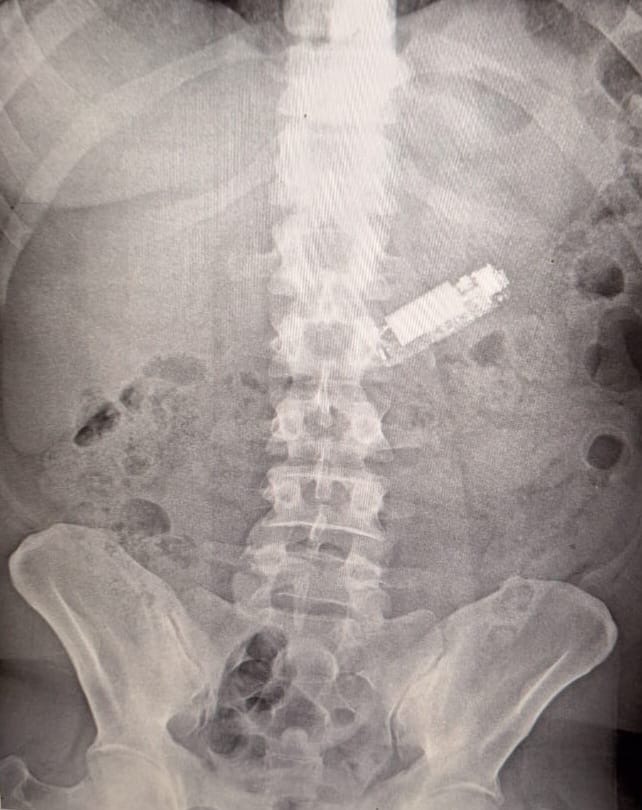

وأوضح الدكتور غنيم أن وحدة الطوارئ استقبلت مريضًا في العقد الرابع من العمر يعاني من وجود هاتف محمول داخل بطنه بعد أن ابتلعه بطريق الخطأ قبل 5 شهور. وتم إجراء الفحوصات الطبية اللازمة، بما في ذلك أشعة على البطن التي أكدت وجود الهاتف في المعدة. وبعد إجراء منظار استمر لمدة ساعة، تم استخراج الهاتف بنجاح، وخرج المريض من المستشفى بعد استقرار حالته الصحية.